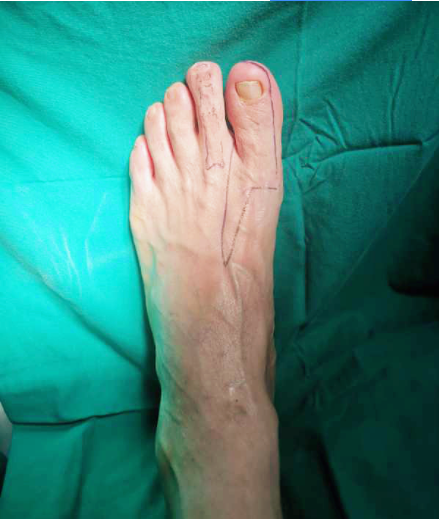

手指再造术前设计

经过多方打听和寻医,最终,曹先生选择了顺德和平外科医院进行右手示指再造,手中心雷彦文、吴祥主任医疗团队为其诊疗,最终决定将采用左足第二趾联合左足踇甲瓣移植再造右示指术。

经过与吴祥主任团队一个多月的评估、手术设计讨论,曹先生最终选择相信和平医院。从早上十点到下午四点,吴祥主任与其医疗团队忙活了6个多小时,终于成功将曹先生的左足足趾移植到右手示指上。

吴祥主任介绍,“右手示指Ⅳ度缺损”,面对这样一名功能和外观要求度高的患者,为了尽量保持示指的长度、功能、外观,采取了“建房子”的手术方法,简单来说就是“缺什么补什么”,例如:缺骨头缺关节,就补骨头补关节;缺皮肤缺指甲,就补皮肤补指甲。通过在身体其他部位取材,把”房子”内部填充完整。对比传统的足趾搬家再造,“建房子”理念的再造难度提高了很多。

他进一步解释,第二脚趾骨关节的功能是恢复手指的关节活动度;而大脚趾踇甲皮瓣的功能是尽可能让手指达到正常示指的外观。